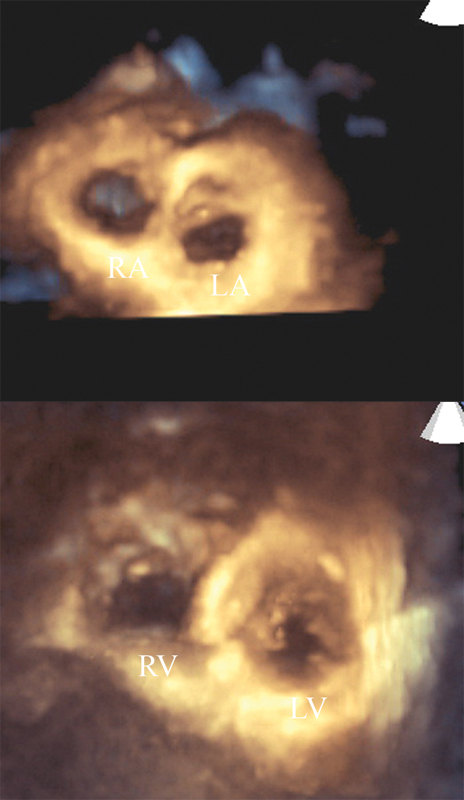

فحوصات تشخيصية لبعض امراض القلب والشرايين التاجية